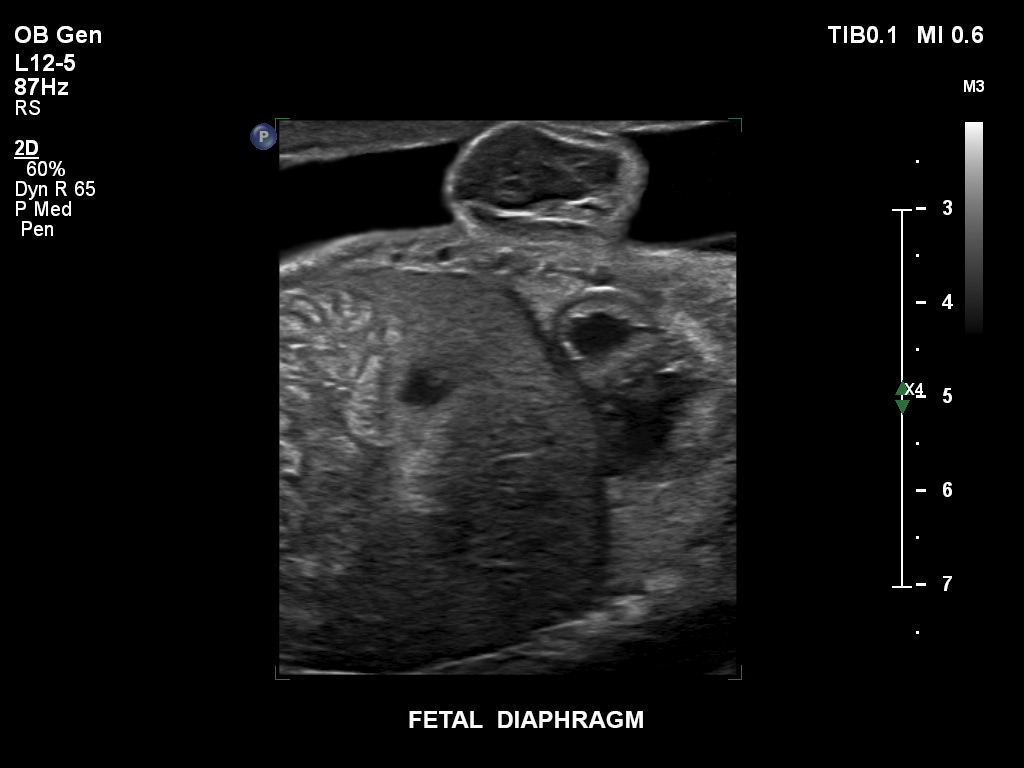

Die EPIQ-Produktreihe mit ausgereiften Schallköpfen erfüllt die Anforderungen auch Ihrer anspruchsvollsten gynäkologischen Untersuchungen und während der gesamten Schwangerschaft.

• C9-2 PureWave-Breitband-Convex-Schallkopf für Hochfrequenz-Bildgebung in der Gynäkologie und der Geburtshilfe, insbesondere für die Untersuchung im Hinblick auf mögliche Anomalien im ersten Schwangerschaftstrimester